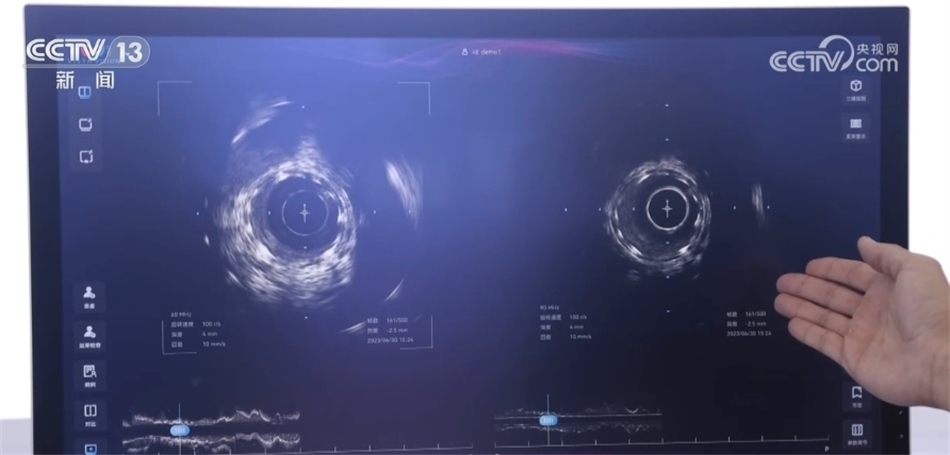

總臺(tái)央視記者 褚爾嘉:這里是一個(gè)傳統(tǒng)的血管的超聲圖像,我們可以看到血管的全貌。右邊這里是一個(gè)工作頻率高達(dá)100兆赫茲的超高頻的血管內(nèi)超聲圖像,通過技術(shù)升級(jí),現(xiàn)在我們可以更加清晰地看到冠狀動(dòng)脈的精細(xì)結(jié)構(gòu),這也是目前世界上清晰度最高的一個(gè)血管內(nèi)的超聲圖像。

中國(guó)科學(xué)院深圳先進(jìn)技術(shù)研究院研究員 馬騰:在醫(yī)學(xué)影像領(lǐng)域,圖像的分辨率和深度是不可兼得的。我們創(chuàng)新性地將一個(gè)超高頻的探頭和一個(gè)傳統(tǒng)的探頭融入到一個(gè)導(dǎo)管里,在不改變導(dǎo)管尺寸的情況下,可以為醫(yī)生提供一個(gè)大深度、高精度二者兼得的圖像。對(duì)于一些冠狀動(dòng)脈急性病癥,包括斑塊的診斷以及介入手術(shù)的治療,會(huì)給醫(yī)生提供一個(gè)更加全面、更加有效的醫(yī)療影像學(xué)工具。